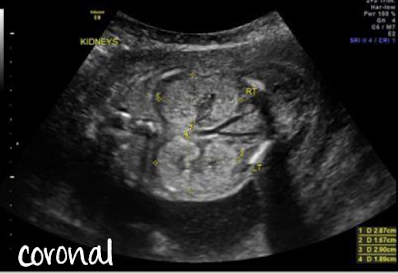

what plane was this taken in?

coronal